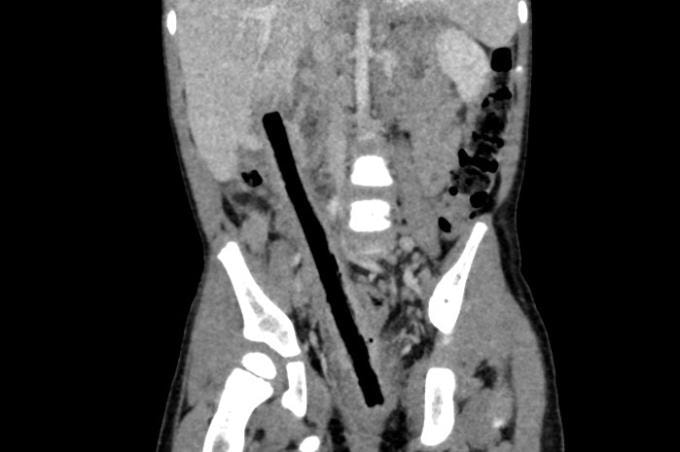

Ngày 30/9, BS.CK1 Nguyễn Hiền, Khoa Ngoại tổng hợp, Bệnh viện Nhi đồng 2, cho biết CT scan cho thấy ổ bụng bệnh nhi có dị vật dài 16 cm nằm từ trực tràng lên tới gan. Nội soi xác định cành cây đã xuyên qua trực tràng, ruột non và tá tràng, gây viêm dính nhiều vị trí, khiến phẫu thuật trở nên phức tạp.

Êkíp tiến hành mổ mở, bóc tách theo đường đi của dị vật, giải phóng các đoạn ruột dính, đồng thời bảo tồn mạch máu, thần kinh và niệu quản. Sau 4 giờ phẫu thuật, các bác sĩ lấy ra nguyên vẹn cành cây dài 16 cm, xử lý cầm máu, khâu vết thương và làm hậu môn tạm.